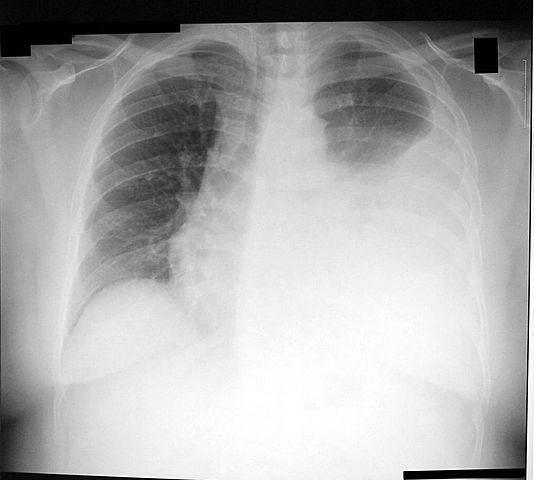

• I suffered pneumonia with pleural effusion

I suffered pneumonia with pleural effusion

This was the second tijme my life was in danger. When i was in the hospital due the peritonitis. My left lung was 90% full of water and i almost die. Fortunately i survives :) And from all this experience i got a lot of knowledge and lessons for my life.